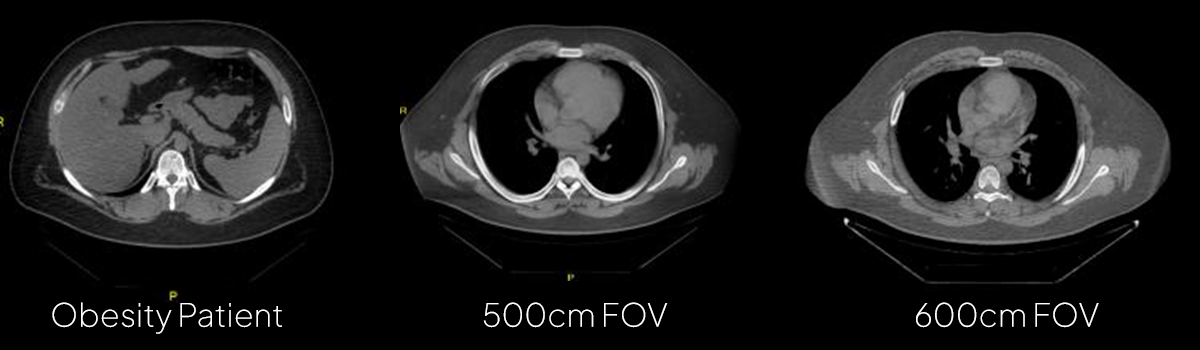

Large Bore for Wide Applications Positioning and scan flexibility for complex-type patient

76cm scan space/250kg table capacity and 21Lp/cm Resolution is easy to position obese patients comfortably without compromising dose and image quality

Image Reconstruction Recon FOV: 50~500mm. ,50~650mm (Extended)